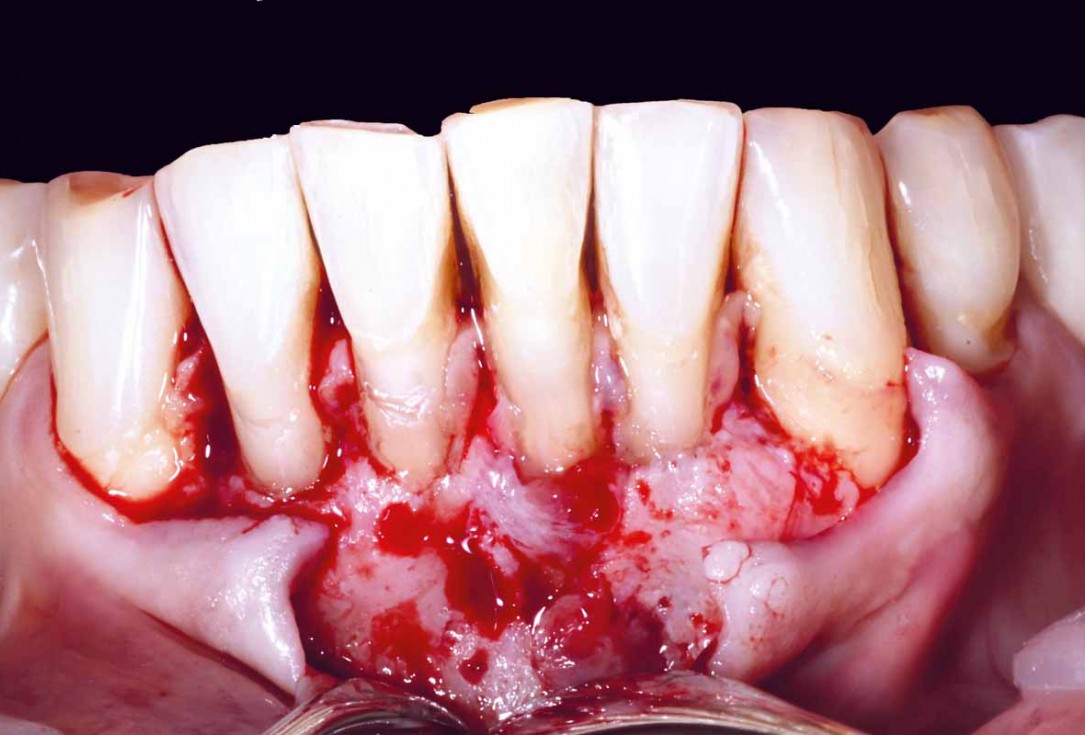

Pre-operative situation showing tooth 21 with deep periodontal pocket. Tooth presented with mobility grade III.